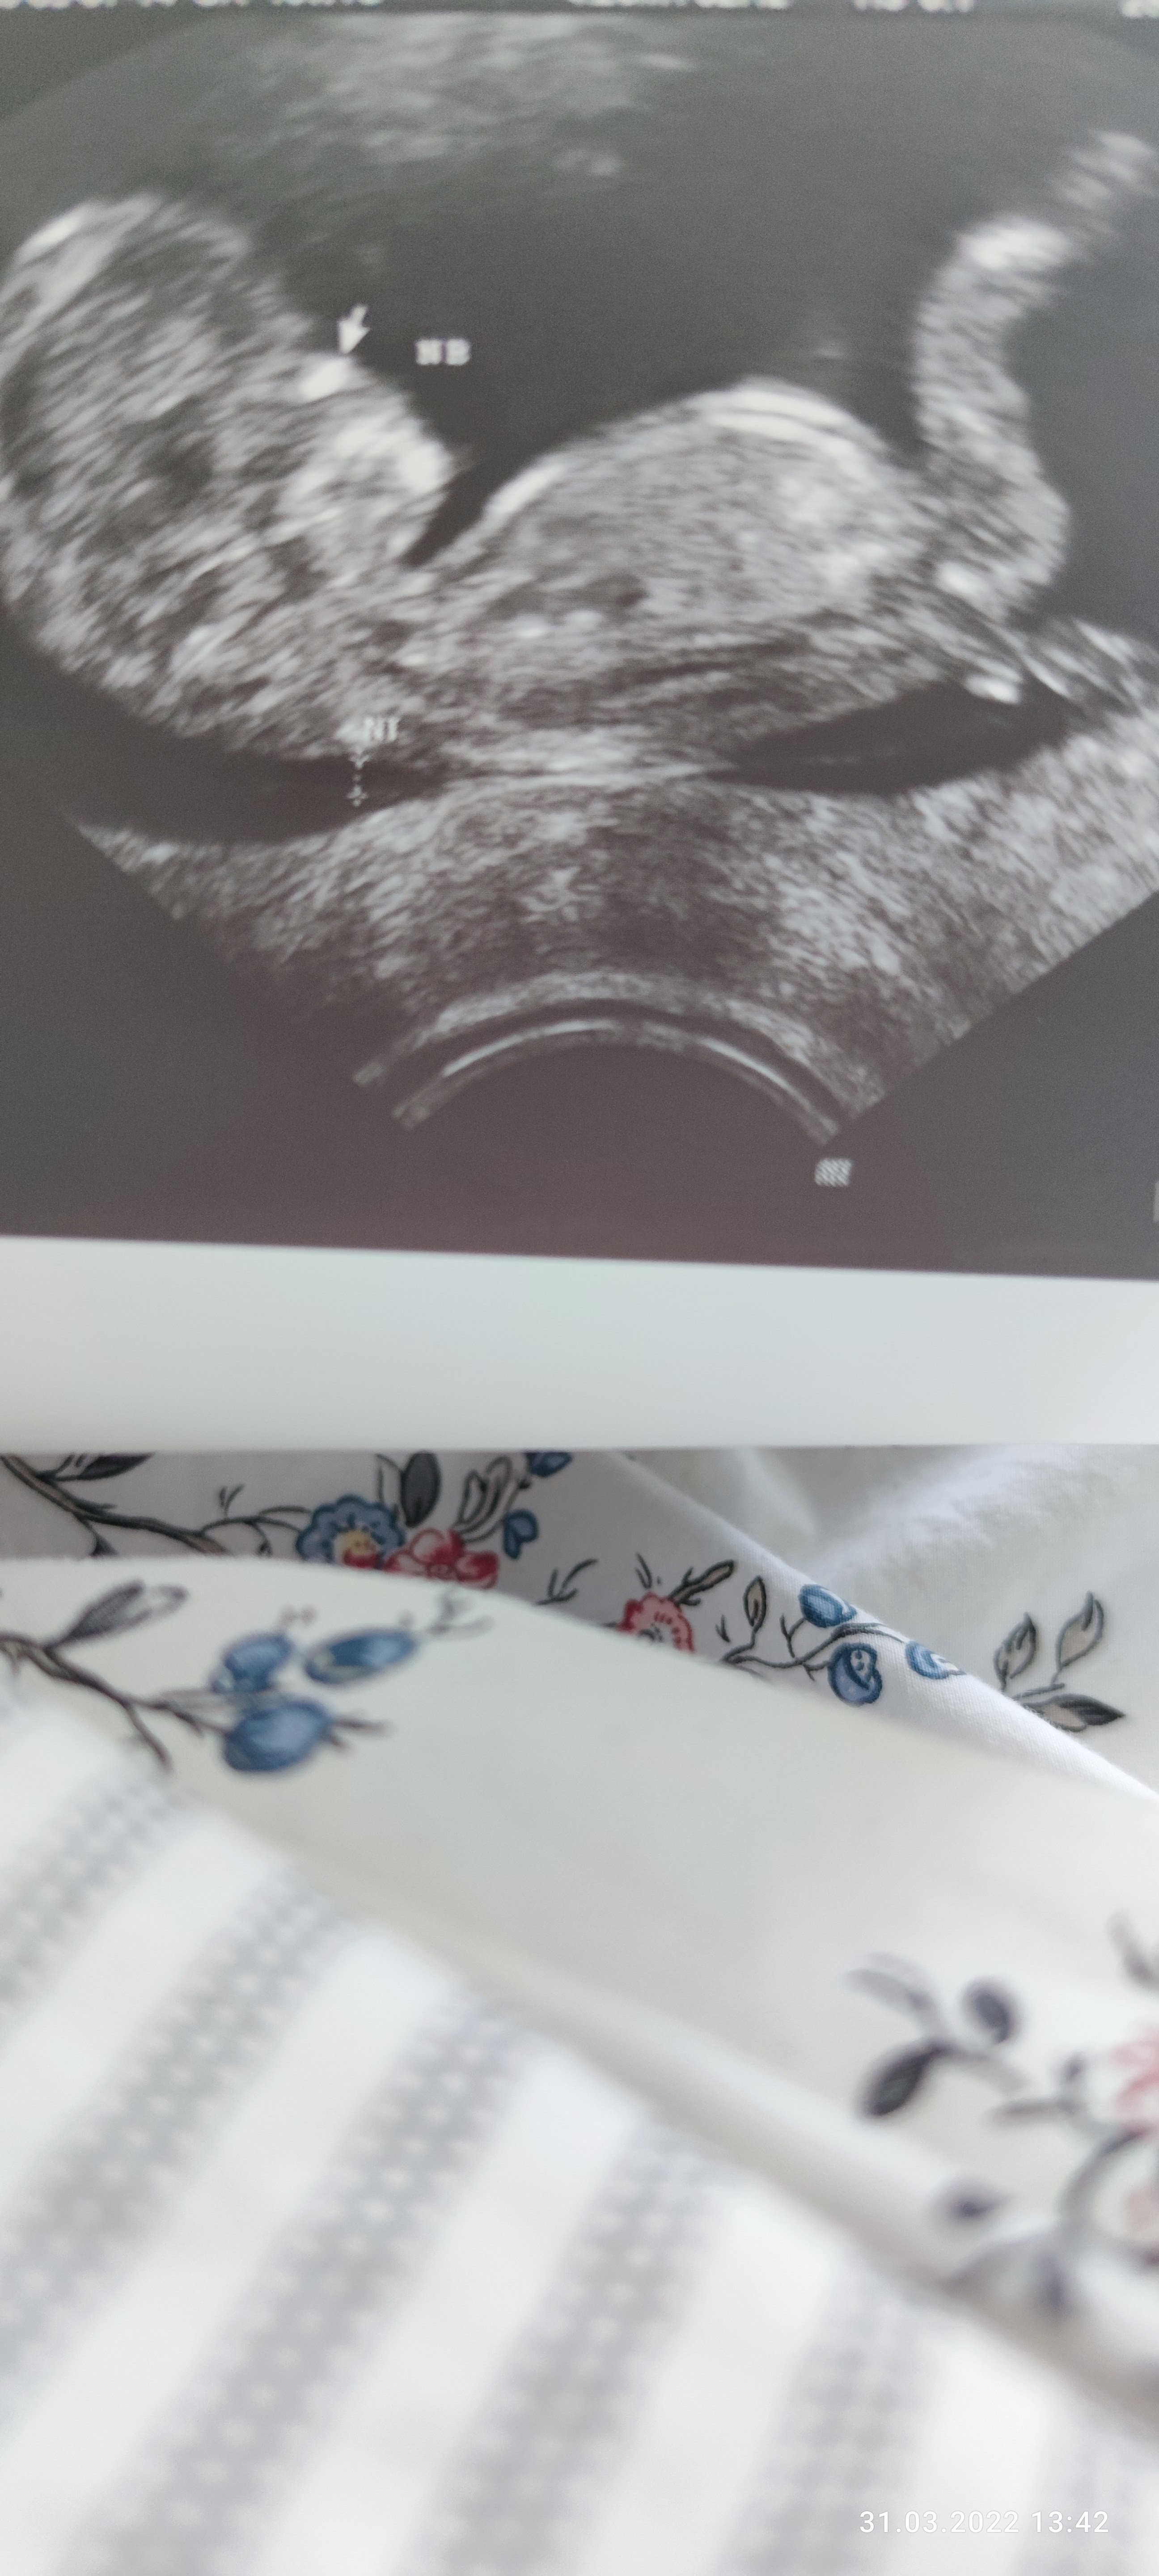

Zdjecie z 10 tygodnia wg. Miesiaczki, z usg 11 tydzien.

Lekarz twierdzi, ze chlopak( powiedzial, ze przypuszcza). Mi tez sie tak wydaje. A jakie jest Wasze zdanie? Czy takowe narzady moga moze jednak nalezec do pannicy?